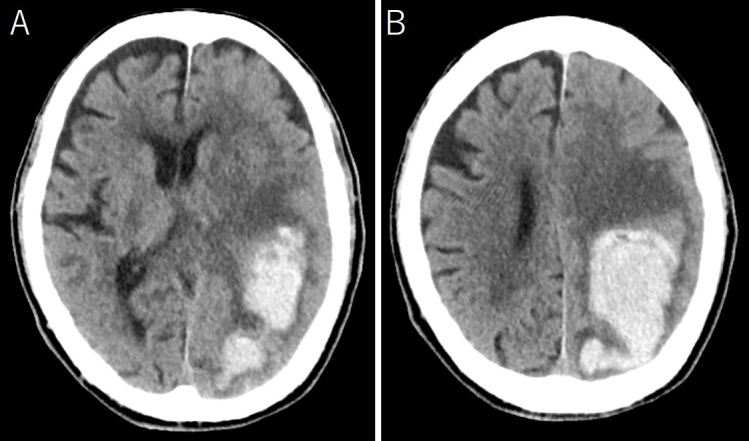

Porencephalic cysts are very rare in adults. Herein, we present a case of an 88-year-old man with a symptomatic expanding porencephalic cyst after intracerebral hematoma evacuation. He was admitted because of disturbed consciousness and right hemiparesis. A computed tomography (CT) showed a large subcortical hematoma in the left parietal lobe. Hematoma evacuation was performed, his consciousness level improved but gradually deteriorated. Follow-up CT revealed a new cystic lesion with perifocal edema at the hematoma site, with progressive expansion of the cyst. Cyst drainage and -peritoneal shunt placement were performed on postoperative day 14; consequently, his symptoms improved. Considerably, a porencephalic cyst have developed because the cerebrospinal fluid flowed into the closed hematoma cavity from the ventricle owing to the osmotic pressure difference between the ventricle and the hematoma cavity.